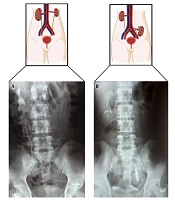

Renovascular Hypertension and Seemingly Non-functioning Kidney Renewed Following Auto-transplantation: Pearls from Over Two Decades of Follow-up

Afarin Neishabouri,

Parham Torabinavid,

Abdol-Mohammad Kajbafzadeh*